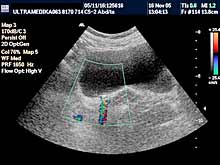

Pregledi abdomena

Standardni pregled podrazumeva pregled svih organa stomaka:

jetra, žučna kesa, žučni putevi, pankreas, slezina, bubrezi, limfne

žlezde,

cevasti organi, veliki krvni sudovi,

pleuralni prostori, prednji trbušni zid. |